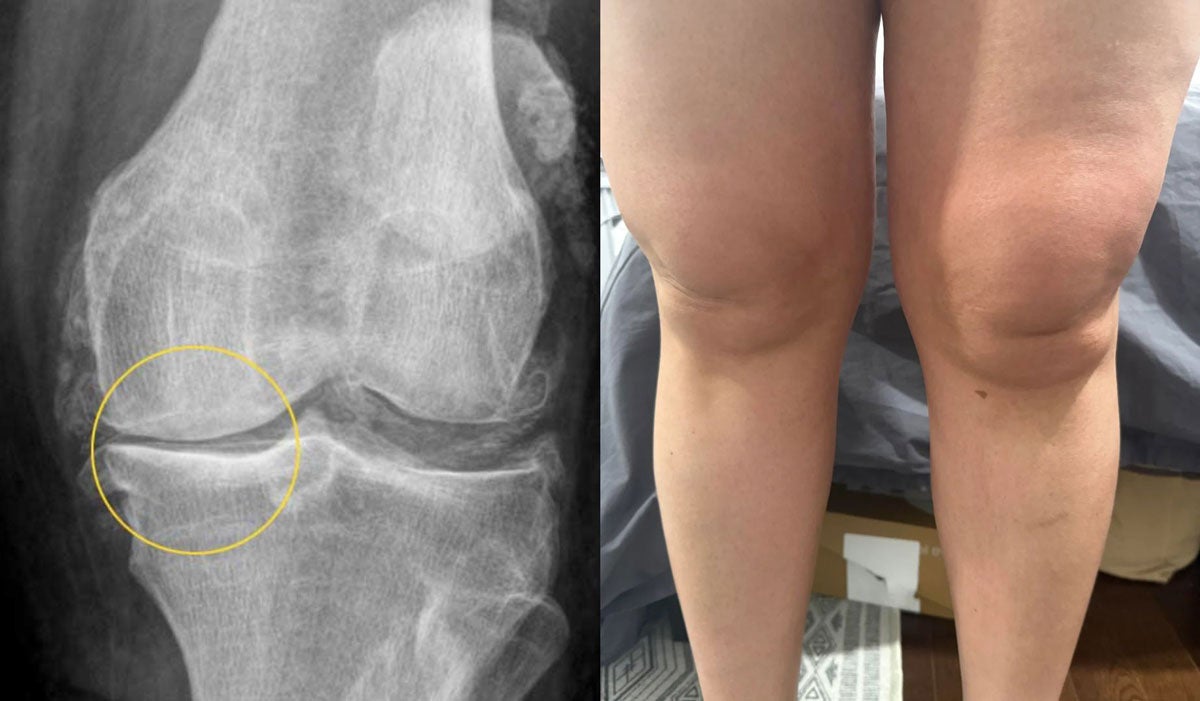

Als die MRT-Bilder auf dem Monitor erschienen, war ich ehrlicherweise ziemlich geschockt:

Deutliche Arthrose im Knie, erste Anzeichen auch in der Hüfte.

Das Knie von Marion im entzündeten Zustand

Marion blickte auf die Bilder und sagte: „Sag es mir ehrlich, wie schlimm ist es?"

Ich wusste nicht, was ich sagen sollte. Ein solches Stadium sehe ich normalerweise erst ab 65+ Jahren.